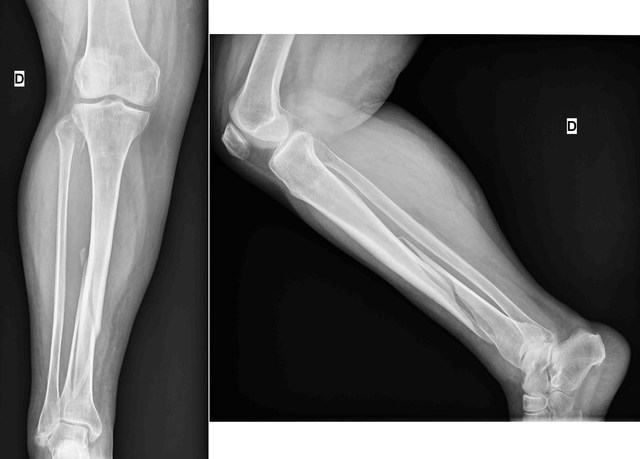

en prácticas de un entrenamiento muy exhaustivo jugando con las inferiores del cortulua; un compañero en el cierre de una pelota me fracturo la rodilla derecha esto previo a un partido contra el deportivo Cali; la valoración hecha por los galenos del club cortulua fue que no podría jugar futbol profesional debido a la alta competencia y a el ritmo en los entrenamientos. Para ver mi vida desde otra óptica ingreso a estudiar leyes en la USC. En la cual hice 3 semestres.